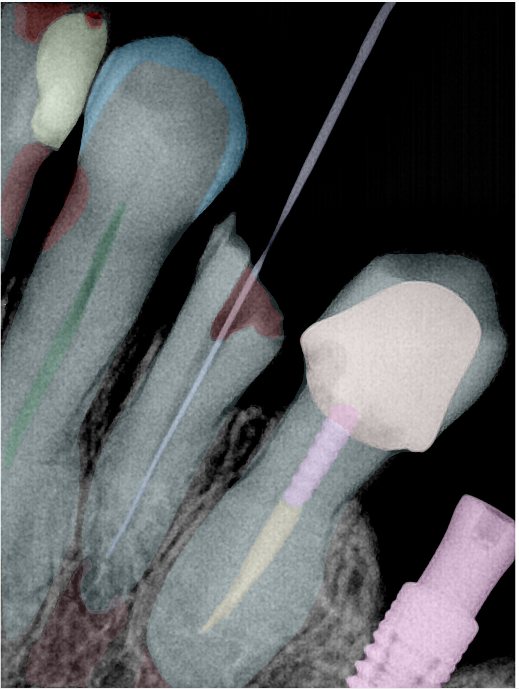

CR/DR 牙齿分割阶段记录

当前进展

- 完成了 CR/DR 牙齿相关分割训练

- 当前结果已经达到阶段预期,但仍有细节问题需要继续处理

相关测试

遇到的问题

- 训练过程中出现过 mask 下移问题

- 部分结果会出现 box 填充异常

- mask 边缘仍然有比较明显的锯齿感

参考

第二版算法问题测试

结论:修复类出现了不鲁棒的情况,后续需要加入轮廓的扩充数据进行增强。

第三版算法分辨率效果比较

| 编号 | 原图 | 第一版 | 第二版 | 第三版 1216x1600 | 第三版 768x1024 | 第三版 1120x1120 |